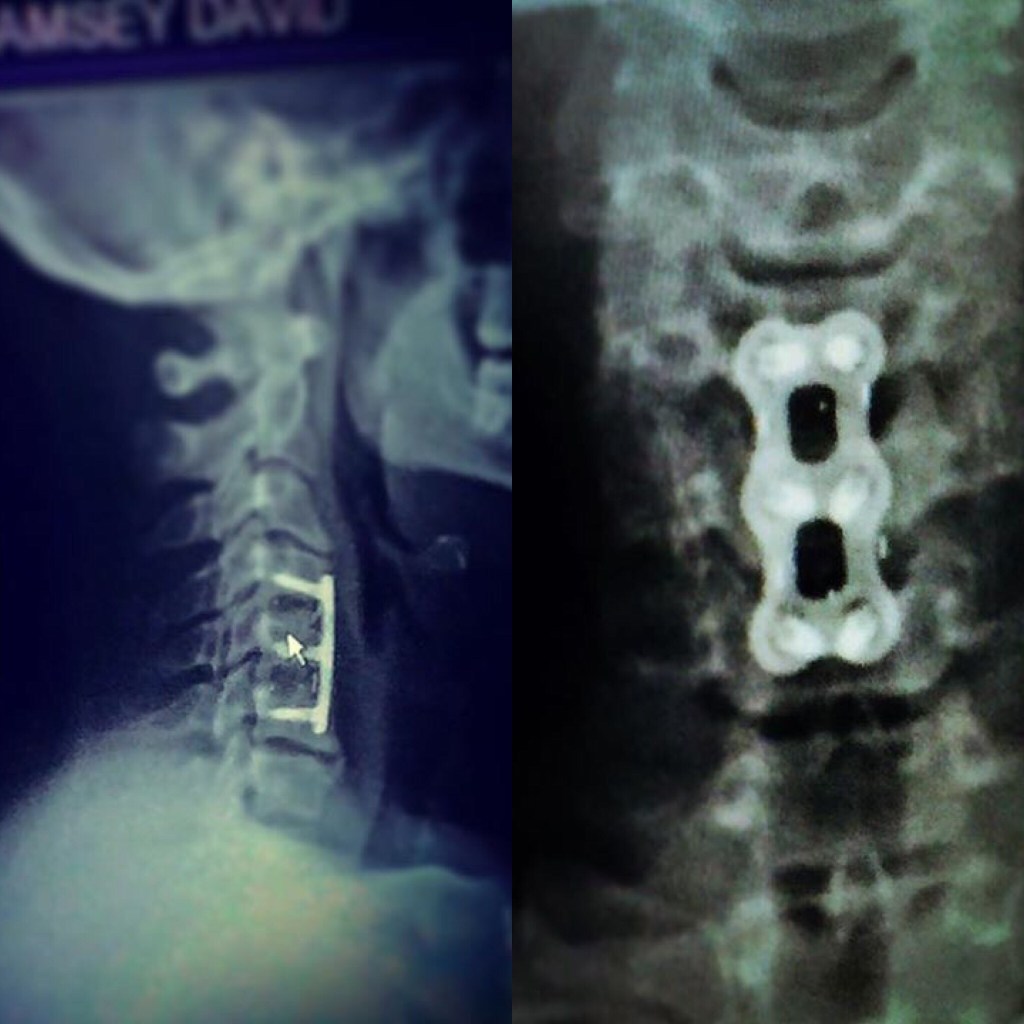

“Mine Proves It” my dna 🧬 is over 40,000 years old!” David Ramsey